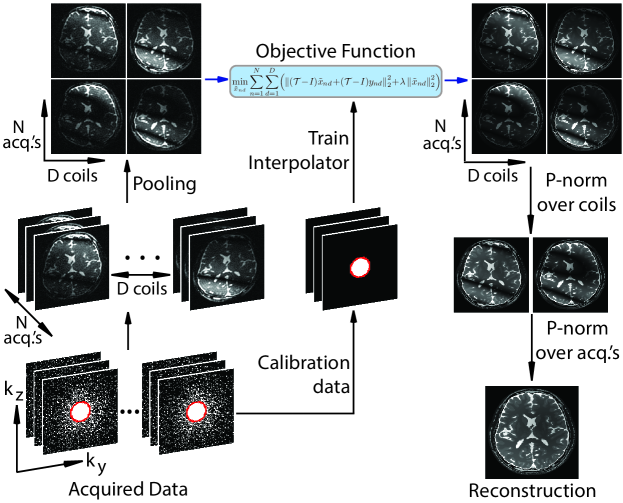

Here, we propose an improved framework for phase-cycled bSSFP imaging, reconstruction by calibration over tensors (ReCat), that utilizes correlated information simultaneously across multiple coils and acquisitions (Fig. 1). ReCat is based on a joint encoding model: the bSSFP image for a given coil and phase-cycle is taken to be spatially modulated by a respective pair of coil sensitivity [11, 21] and bSSFP profile [22, 17]. A tensor-interpolation kernel comprising coil and acquisition dimensions is estimated from calibration data. This kernel is then used to linearly synthesize unacquired samples. Compared to kernels trained only on coil or on phase-cycles, the ReCat kernel aims to optimize use of aggregate information across both dimensions.

Here we propose to accelerate multi-coil multi-acquisition bSSFP imaging via a new technique named reconstruction by calibration over tensors (ReCat). Unlike PI or PE-SSFP, the proposed approach utilizes correlated information simultaneously across the coil and acquisition dimensions. For this purpose, ReCat casts on Eq. 1 a tensor encoding model based on both coil sensitivities and bSSFP profiles:

where denotes the ideal bSSFP image devoid of modulations due to both bSSFP profiles and coil sensitivities. Leveraging this model, ReCat recovers unacquired k-space data in terms of collected data aggregated across coil and acquisition dimensions (see Fig. 2). First, a tensor-based interpolation kernel is estimated from fully-sampled calibration data. This kernel is then used to linearly synthesize missing k-space samples.

Interpolation kernel: ReCat uses an interpolation kernel to estimate each unacquired k-space sample as a weighted combination of neighboring data in all coils and acquisitions:

Reconstruction: ReCat recovers missing k-space samples based on the interpolation operator . Inspired by the SPIRiT method (iterative self-consistent parallel imaging reconstruction) for multi-coil imaging [21], a self-consistency formulation is used that enforces consistency of both acquired and recovered data with Eq. 7. Accordingly, ReCat solves the following optimization problem:

All reconstruction methods produced separate images from each acquisition and each coil. Individual images were then combined with the p-norm method to maintain favorable performance in artifact suppression and SNR efficiency [31]. Combination was performed with across coils, and with across acquisitions (see Sup. Fig. S2). Two different orders of combination were tested: first across coils then acquisitions, and first across acquisition then coils. No significant difference was observed due to combination order.